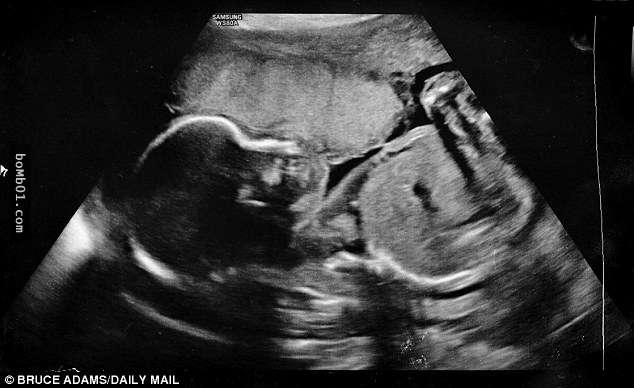

▼28歲的露依絲(Louise Adams)和丈夫生活在英國的史丹佛郡,他們本來都迫不及待迎接小兒子喬瑟夫(Joseph)的到來,但在22週的產檢卻得知,露依絲的羊水提早破裂了,胎兒恐怕無法存活。

▼在露依絲羊水破裂後,醫生警告他們胎兒只剩5%的存活率,而且因為喬瑟夫還沒來到比較穩定的24週,所以他們無計可施。露依絲和丈夫都對這樣的結果相當震驚,但他們也同時決定,絕不放棄這個孩子。